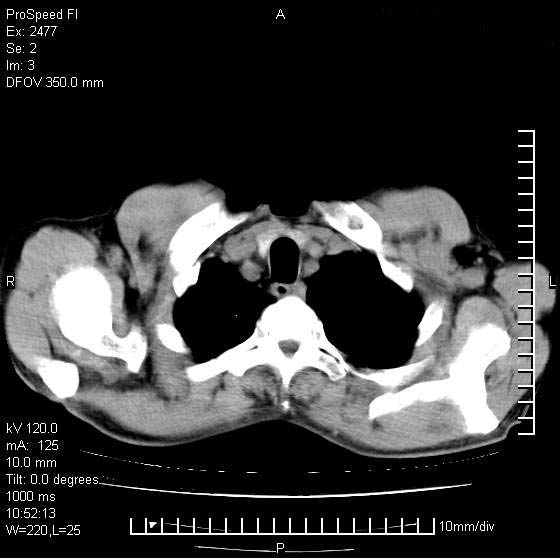

以下是引用天南地北在2007-10-9 14:29:00的发言:[br]1:右上肺结核[br]2:右肺下叶肿块:不支持肺癌,首先考虑炎性病变-肺脓疡可能性大[br]理由:1:临床病史支持,肺脓肿症状不明显应该是不规则服药造成。[br] 2:肿块边缘模糊,周围可见炎性渗出,长毛刺,内见支气管征,不过有点不规则。[br] 我感觉下肺癌这个诊断有点偏左,建议积极抗炎治疗后复查

以下是引用卜一在2007-10-9 15:55:00的发言:[br][br] [br] 1:右上肺结核[br]2:右肺下叶肿块:不支持肺癌,首先考虑炎性病变-肺脓疡可能性大[br]理由:1:临床病史支持,肺脓肿症状不明显应该是不规则服药造成。[br] 2:肿块边缘模糊,周围可见炎性渗出,长毛刺,内见空气支气管征,不过有点不规则。[br] 我感觉下肺癌这个诊断有点偏左,建议积极抗炎治疗后复查![br]支持! [br] [br] [br]

以下是引用wxy7406在2007-10-9 21:02:00的发言:[br]结合临床病史首先考虑感染性病变,但周围型肺癌不能除外,1.患者年龄偏大2.临床有咯血3.(也觉得是最重要的一点)病灶内有偏心性空洞。

以下是引用王仕学在2007-10-9 13:48:00的发言:[br]右下肺周围性肺癌可能性大,最好活检吧

以下是引用hhcckk在2007-10-9 15:18:00的发言:[br]右上肺病灶考虑结核,病灶多种形态并存(纤维化、增殖性病灶并存)[br]右下肺病灶比较难说,个人意见更趋向于“天南地北”的诊断----肺脓肿[br]1、病人有明显的寒战,高热,肿瘤病人很少出现[br]2、病灶周围的肺纹理走向柔和,没有肿瘤病灶常见的集束征[br]3、病灶边缘的毛刺较长,恶性肿瘤多为短毛刺[br]痰中血丝和病人的年龄是两个不利于良性肿块的因素,建议早点活检

以下是引用ydx_74在2007-10-9 15:53:00的发言:[br]右上肺结核,右下中心性肺癌可能大,肺门淋巴结肿大。